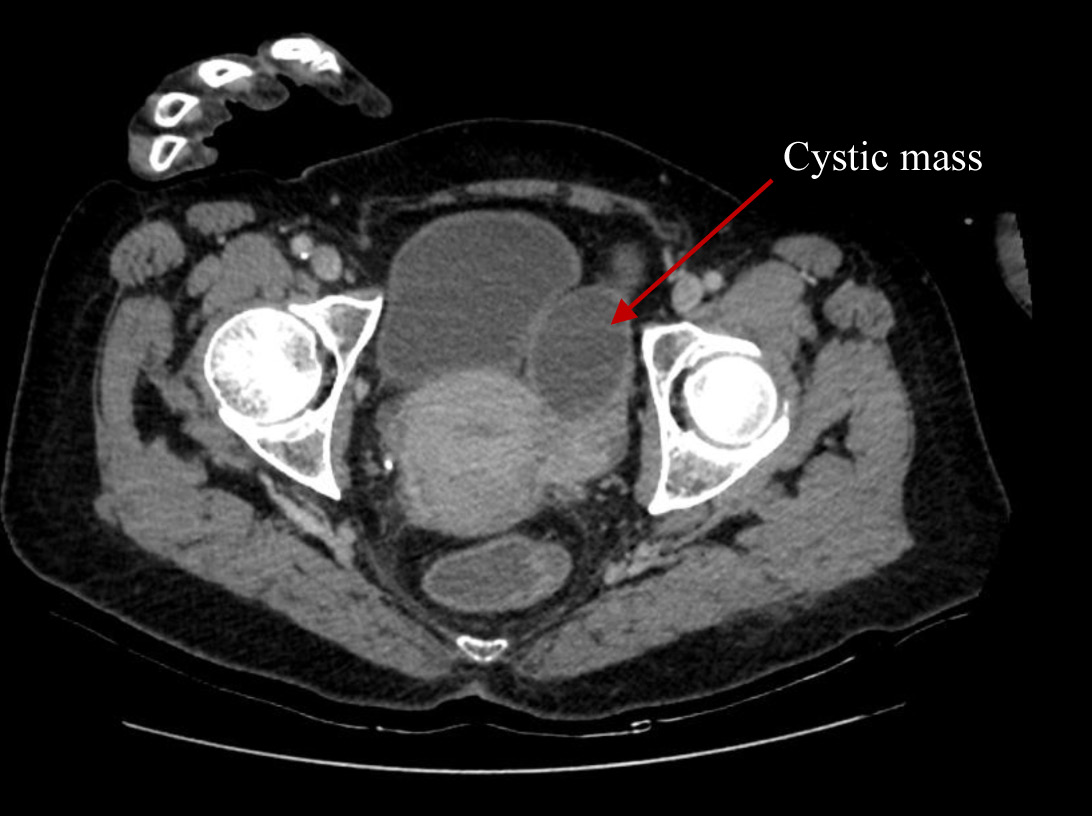

Cystic masses, measuring 6.8 × 6.6 cm in the right adnexa and 7.8 × 5.1 cm in the left adnexa were detected during transvaginal sonography. Computer tomography (CT) of the abdomen and pelvis (Figure 1 and 2) demonstrated abnormal changes in both ovaries. Size of multiloculated cystic lesion in the right ovary was 6.8 × 6.6 cm and 7.8 × 5.1 cm in the left ovary. A small amount of free fluid was found in the pelvic cavity along with thickened pelvic peritoneum.

Figure 1. CT report of abdomen and pelvis. Cystic mass in the right adnexa of uterus (red arrow).